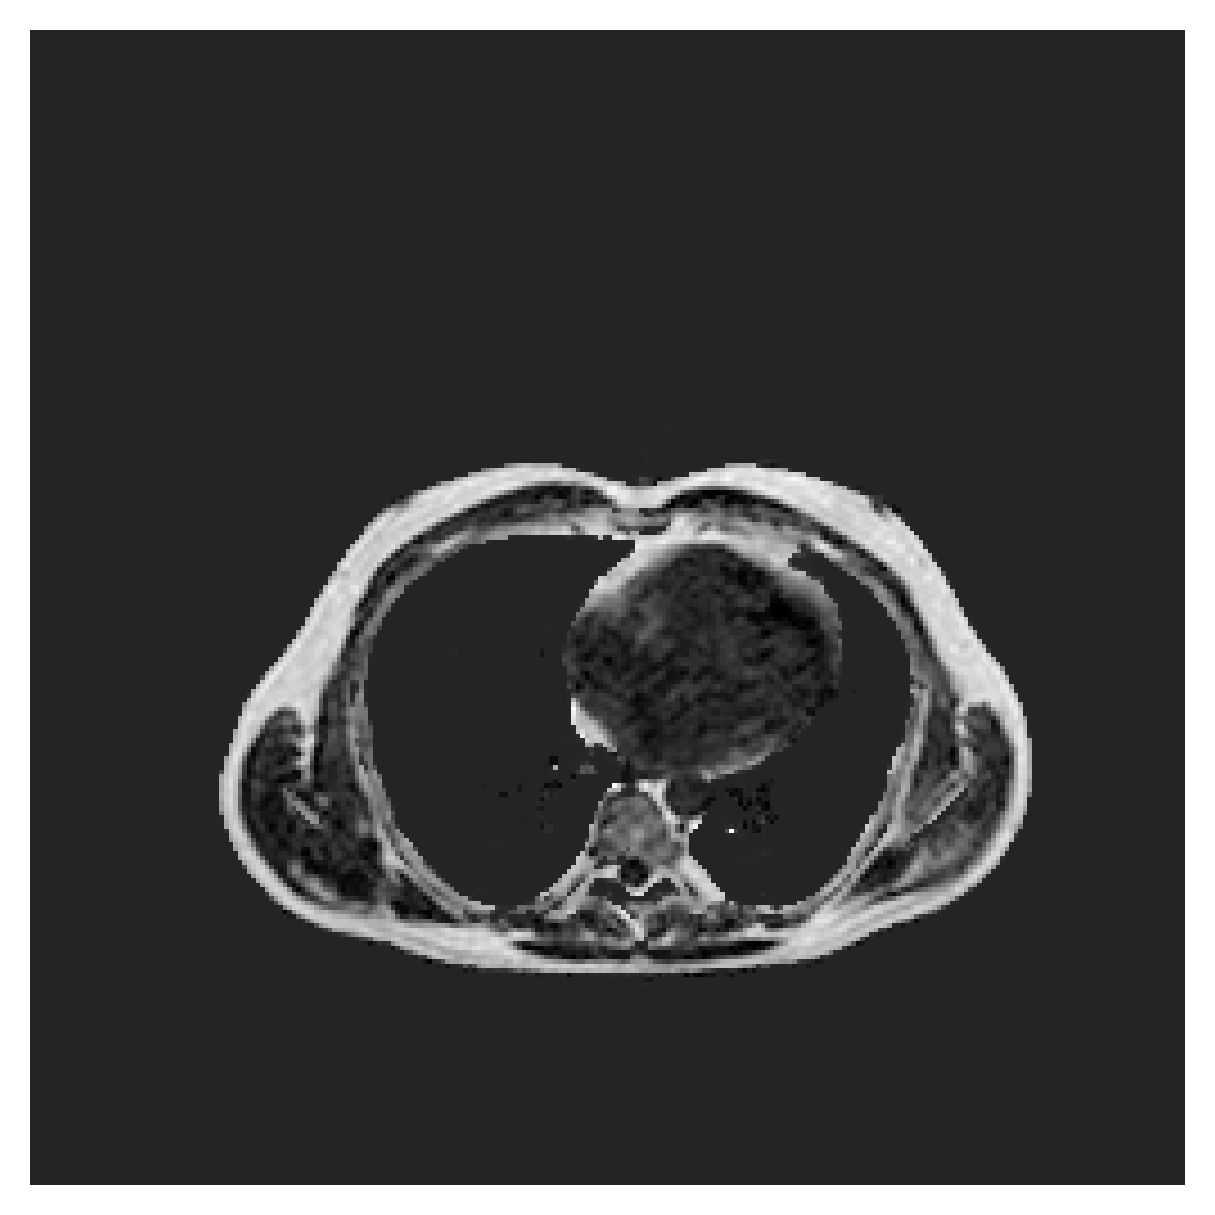

POEM

The Prospective investigation of Obesity, ENergy production and Metabolism (POEM) is a local (not currently publicly available; PI: L. Lind, see [22] for details) cohort of whole-body fat/water separated MR images. Full annotations of the liver, kidneys, bladder, pancreas and spleen are available for 50 subjects, providing a challenging segmentation dataset with heavily imbalanced classes of varying shapes. The resolution of the data is anisotropic, with reconstructed voxel size of in left-right, anterior-posterior and foot-head directions, respectively. For additional technical details regarding the acquisition and specifications of the images see [22].